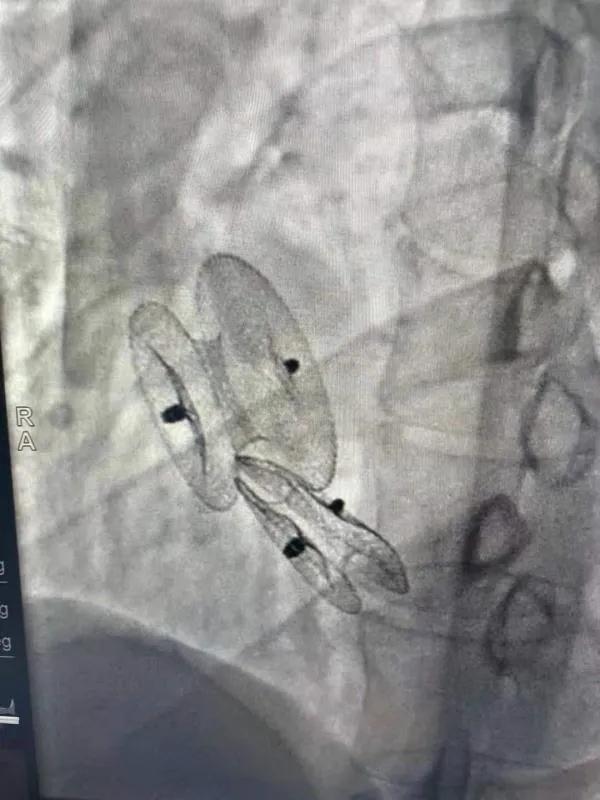

先天性心臟病房間隔缺損呈多孔型怎么辦?患者并非只能選擇開(kāi)胸手術(shù)。近日,西安國(guó)際醫(yī)學(xué)中心醫(yī)院心臟病醫(yī)院成功開(kāi)展一例雙孔房間隔缺損雙傘介入封堵術(shù)。

患者是位27歲的年輕女性,經(jīng)常感到心慌,心臟超聲發(fā)現(xiàn)房間隔缺損,并且房間隔缺損呈雙孔型,大的約14mm,小的約9mm,兩個(gè)缺損間相隔較遠(yuǎn),介入封堵難度非常大。

在詳細(xì)了解患者病情,仔細(xì)閱讀患者影像資料后,曾廣偉主任已經(jīng)有了清晰的手術(shù)策略。在精心的準(zhǔn)備和團(tuán)隊(duì)的配合下,曾主任順利的利用兩個(gè)封堵器對(duì)房缺進(jìn)行了封堵。